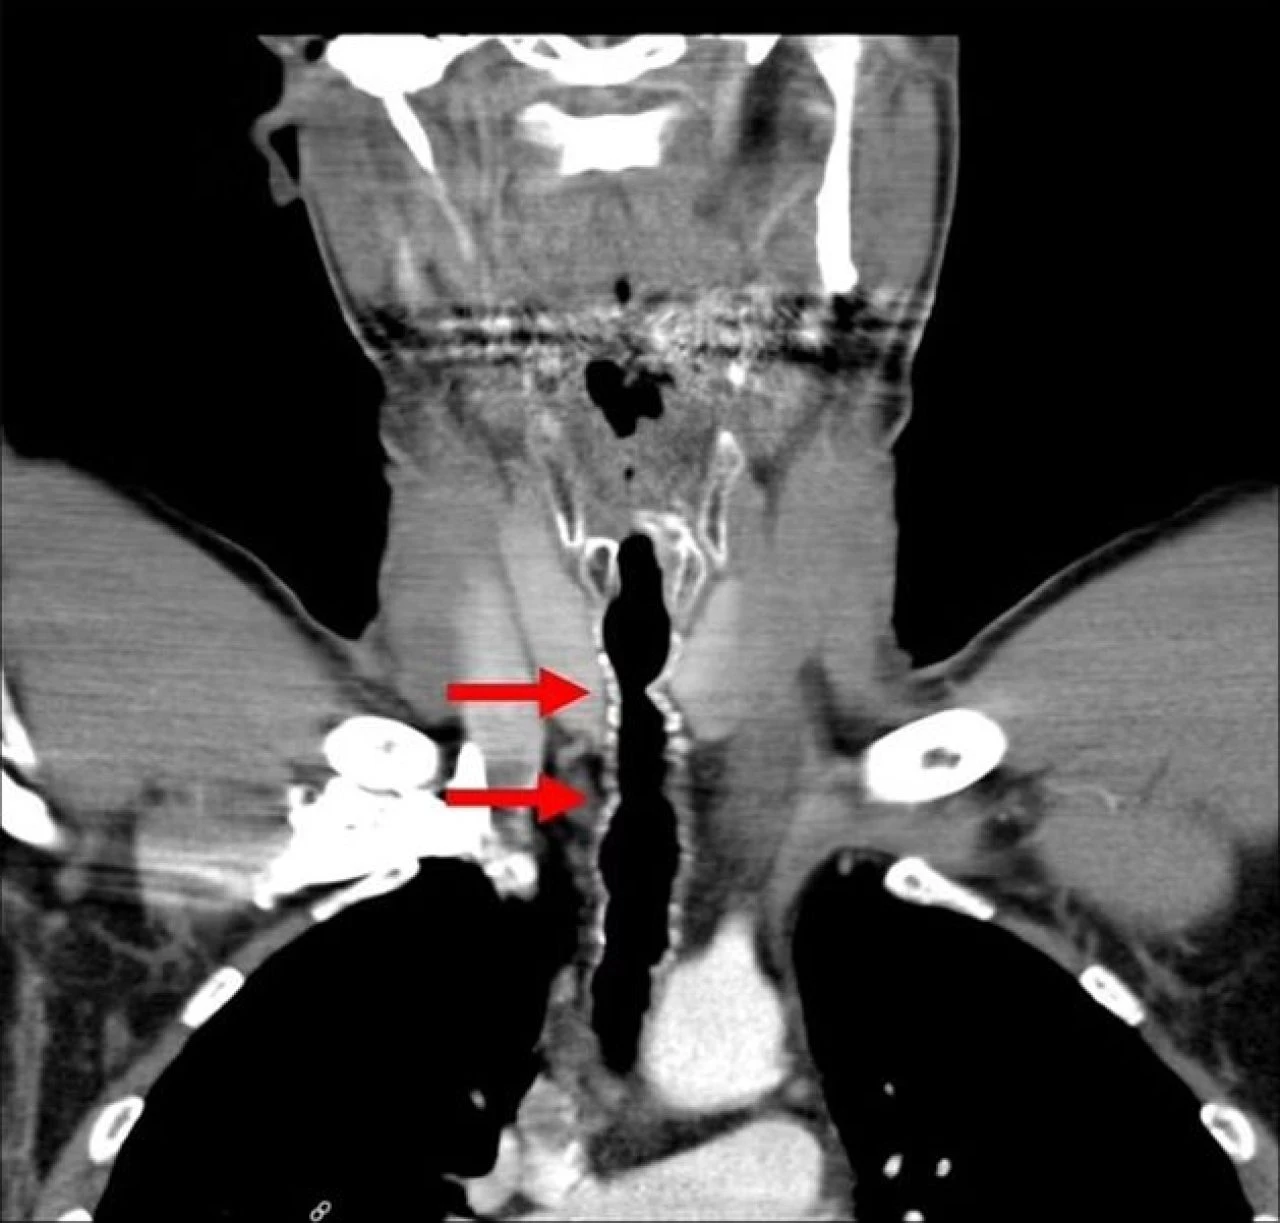

Sağlık görevlileri, solunum yollarına küçük bir kamera göndererek, incelemeye başladılar ve şaşırtıcı bir durumla karşı karşıya kaldılar. Adamın boğazının içinde siyah kılların çıktığı anlaşıldı. Doktorlar, kılları almayı başardılar faka bu geçici bir rahatlama sağladı.

Adamın boğazında çıkan kılların bakteriyle kaplandığı da ortaya çıkınca doktorlar, antibiyotik tedavisine başladılar. Doktorlar, boğazındaki kıllanmanın son derece nadir bir durum olduğunu, senelerce sigara içmesi nedeniyle böyle bir durumla karşılaştığını söylediler.

American Journal of Case Report'ta yazan yazarlar bu olayla ikinci kez karşılaştıklarını dile getirdiler. Boğazdaki kılların 6 ila 9 tane olduğu 5 santimetre boyunda olduğu da açıklandı.